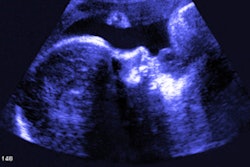

A 3D ultrasound image obtained at 30 weeks in the case of a 34-year-old woman with confirmed Zika virus infection, initially seen for a rash at eight weeks of gestation. Image of the face shows a sloping forehead, compatible with frontal lobe hypoplasia. All images courtesy of Radiology.While microcephaly is a hallmark of Zika, and most fetuses underwent at least one imaging examination that showed head circumference below the fifth percentile, there are a number of other brain abnormalities that indicate the presence of the disease, according the article. These include abnormalities in ventricular size, gray- and white-matter volume loss, abnormalities in the brainstem, and calcifications.